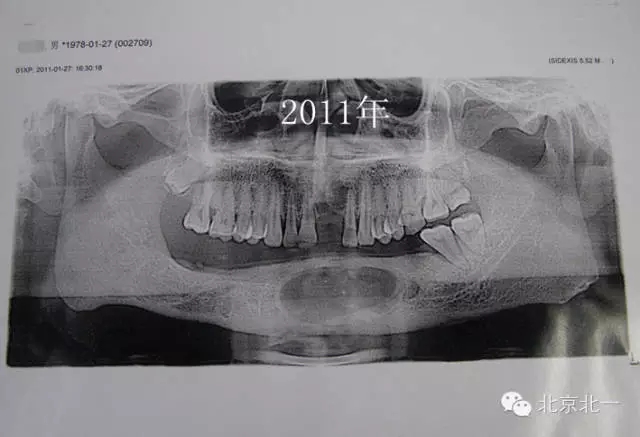

患者男,33歲,左下頜囊腫復發(fā)兩次就診。

圖2、手術(shù)后第一次復發(fā)